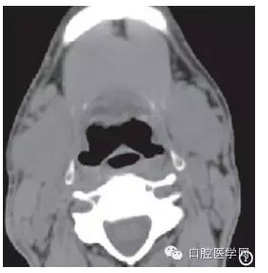

CT檢查:雙側(cè)頜下腺體積明顯增大,邊界清晰,密度增高,其內(nèi)密度均勻,CT值為47Hu,腮腺形態(tài)大小未見(jiàn)明顯異常,密度均勻,CT值為4Hu,CT診斷:雙側(cè)頜下腺體積增大,密度增高,請(qǐng)結(jié)合臨床(圖1)。

圖1 雙側(cè)頜下腺CT平掃:雙側(cè)頜下腺明顯腫大,邊界清晰,密度明顯增高,CT值為47Hu(紅箭頭所示為頜下腺,紅線為右側(cè)頜下腺的長(zhǎng)度)。